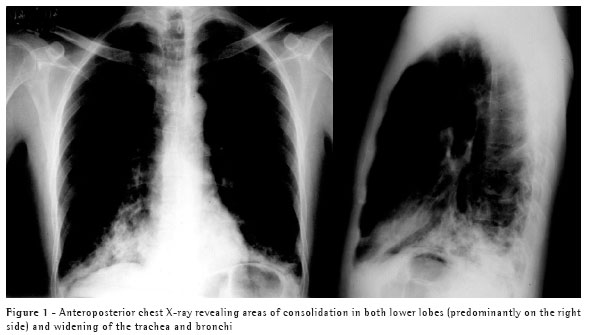

This treatment continued for four weeks, by which time the symptoms had been completely resolved. At that point, the patient was submitted to a computed tomography scan of the chest, which revealed that the areas of consolidation, although smaller in size, persisted in both lower lobes, and confirmed the abnormal widening of the trachea and main bronchi (Figures 1, 2 and 3). In the lower lobes, there was bilateral cylindrical bronchiectasis, which is consistent with a diagnosis of congenital tracheobronchomegaly, or Mounier-Kuhn syndrome. Pulmonary function tests revealed an increase in total lung capacity (123% of predicted) and residual volume (160% of predicted), with no other alterations. Currently, the patient remains asymptomatic, and has daily respiratory therapy sessions. Annual immunization against influenza has been recommended.

Congenital tracheobronchomegaly, or Mounier-Kuhn syndrome, is a rare clinical entity, described for the first time in 1932,(1) and characterized by marked tracheobronchial dilation and lower respiratory tract infections. It is predominantly found in male individuals in their 40s or 50s. Although the etiology of Mounier-Kuhn syndrome remains unknown, it is believed that it is related to a lack of smooth muscle and elastic connective tissue in the trachea and main bronchi, leading to herniation and even to the formation of diverticula between the cartilaginous rings. A finding of bronchiectasis, such as in the case in question, is uncommon.(2-3)

Diagnosis can usually be made by measuring the tracheal diameter, using only data from chest X-rays, in which the trachea can seen in profile and thus the diameter determined. Computed tomography of the chest, however, makes this measurement more precise. The limits are 3 cm for the transverse diameter of the trachea, and 2.4 cm and 2.3 cm for the transverse diameters of the main right and left bronchi, respectively.